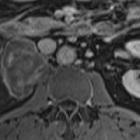

retroperitoneales Ganglioneurom

benignes Ganglioneurom Radiopaedia • CC-by-nc-sa 3.0 • de

MRI

Ganglioneuromas are well-circumscribed masses. They may appear encapsulated, although a true capsule is infrequent . Reported signal characteristics include:

- T1: tends to have homogeneously low or intermediate signal

- T2: tends to have heterogeneously intermediate or high signal

- T1 C+ (Gd): variable ranging from none to heterogeneous enhancement

- ADC: ADC values tend to be higher than that of a neuroblastoma